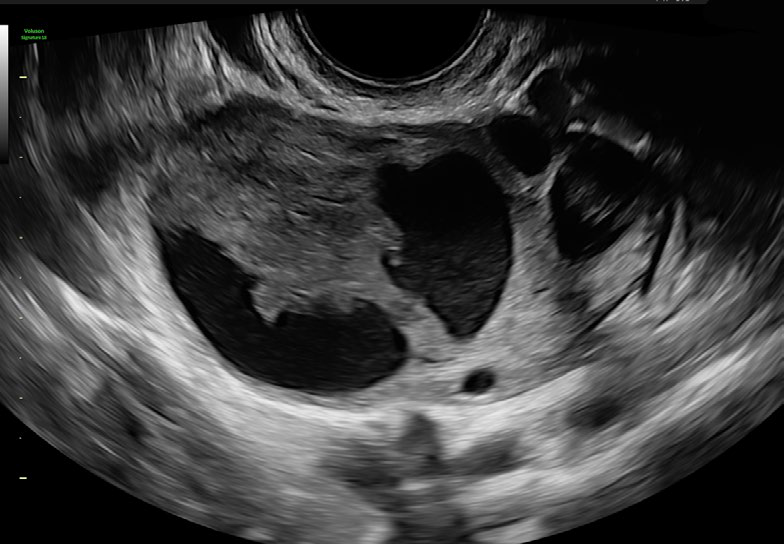

El Voluson Signature 18 se basa en un nuevo motor de imágenes: la arquitectura Voluson Unity, que ofrece velocidades de procesamiento y velocidades de fotogramas más rápidas que nuestros sistemas Signature anteriores. Este hardware y software son la base del sistema y sientan las bases para las capacidades actuales y futuras. Experimente ahora un nuevo nivel de profundidad y claridad.

Procesamiento rápido de volumen 3D/4D

Calidad de color mejorada y mayor sensibilidad